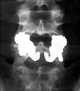

Pars interarticularis defect

Spondylolysis (spon-dee-low-lye-sis) is defined as a defect or stress fracture in the pars interarticularis of the vertebral arch. The vast majority of cases occur in the lower lumbar vertebrae (L5), but spondylolysis may also occur in the cervical vertebrae. [Source: Wikipedia ]